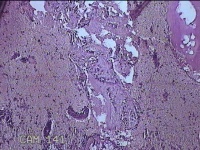

宫腔内容物

性别

女

年龄

50岁

临床诊断

异常子宫出血 子宫腔赘生物待查 子宫肌瘤 疤痕子宫

一般病史

不规则阴道流血25Tina,增多7天。

标本名称

大体所见

灰白暗红色不规则碎组织2.5x1.7x0.8cm一堆。